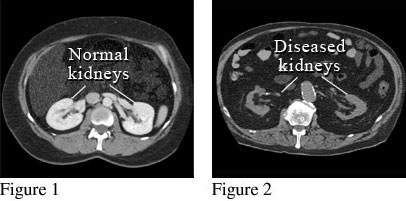

CT Scan of Damaged KidneysCourtesy of Intermountain Medical Imaging, Boise,

Idaho. Figure 1 shows a picture of a computed tomography (CT) scan of two

normal kidneys, looking from the top of the head down. A special dye (contrast

material) was used for this scan. Figure 2 shows a picture from a different CT

scan of two kidneys that are abnormal. These kidneys are small and misshapen

from scarring due to disease. ByHealthwise Staff Primary Medical ReviewerAdam Husney, MD - Family Medicine Specialist Medical ReviewerHoward Schaff, MD - Diagnostic Radiology Current as ofOctober 14, 2016 Current as of: